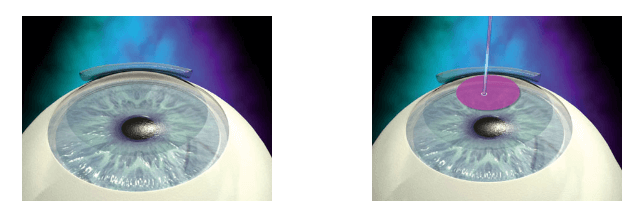

LASIK ή PRK — Ποια μέθοδος είναι καταλληλότερη;

Οι διαφορές των δύο μεθόδων Lasik / PRK όσον αφορά στο τελικό αποτέλεσμα είναι πρακτικά αμελητέες. Η επιλογή της σωστότερης μεθόδου εξατομικεύεται και συχνά επηρεάζεται από προσωπικές επιλογές χωρίς καθαρά επιστημονικά κριτήρια. Για παράδειγμα στις ΗΠΑ το 90% των ασθενών κάνουν διόρθωση της μυωπίας με τη μέθοδο Lasik, ενώ αντίθετα στην Ιταλία το 90% επιλέγει PRK. Τα πλεονεκτήματα κάθε μιας μεθόδου που παραθέτονται παρακάτω στόχο έχουν την καλύτερη ενημέρωση του υποψήφιου ασθενή που σκέφτεται να υποβληθεί σε διαθλαστική επέμβαση στο επίπεδο του κερατοειδούς, δηλαδή διόρθωσης της μυωπίας, αστιγματισμού, υπερμετρωπίας ή πρεσβυωπίας με Lasik ή PRK.

Ο μικροκερατόμος (laser ή μηχανικός) που χρησιμοποιείται στην τεχνική LASIK δημιουργεί έναν κρημνό (flap) που δεν επουλώνεται 100% ποτέ. Συνεπώς, το flap μπορεί θεωρητικά να υποστεί σοβαρό τραυματισμό σε έναν τυχαίο (μικρο)τραυματσιμό του ματιού στο μέλλον. Επίσης, το φλαπ συνήθως ανιχνεύεται σε οποιοδήποτε οφθαλμολογικό έλεγχο στο μέλλον.

Πλεονεκτήματα LASIK (S-Lasik, LASAK ή SBK)

Aν και η τελική όραση είναι η ίδια και μάλιστα σε ορισμένα ποιοτικά χαρακτηριστικά καλύτερη από τη μέθοδο PRK/ASA, η μέθοδος διόρθωσης μυωπίας-αστιγματισμού-υπερμετρωπίας Lasik έχει σαφές προβάδισμα στην ταχύτητα ανάκτησης της όρασης, στην ανάγκη χρήσης κολλυρίων για πολύ λιγότερες ημέρες, στα λιγότερα συνοδά συμπτώματα άλγους, δακρύρροιας, θολερότητας, φωτοφοβίας κατά την πρώτη τουλάχιστον μετεγχειρητική εβδομάδα. Η επάνοδος του ασθενούς την πρώτη κιόλας μετεγχειρητική μέρα στην καθημερινότητα του είναι σαφώς ευκολότερη.